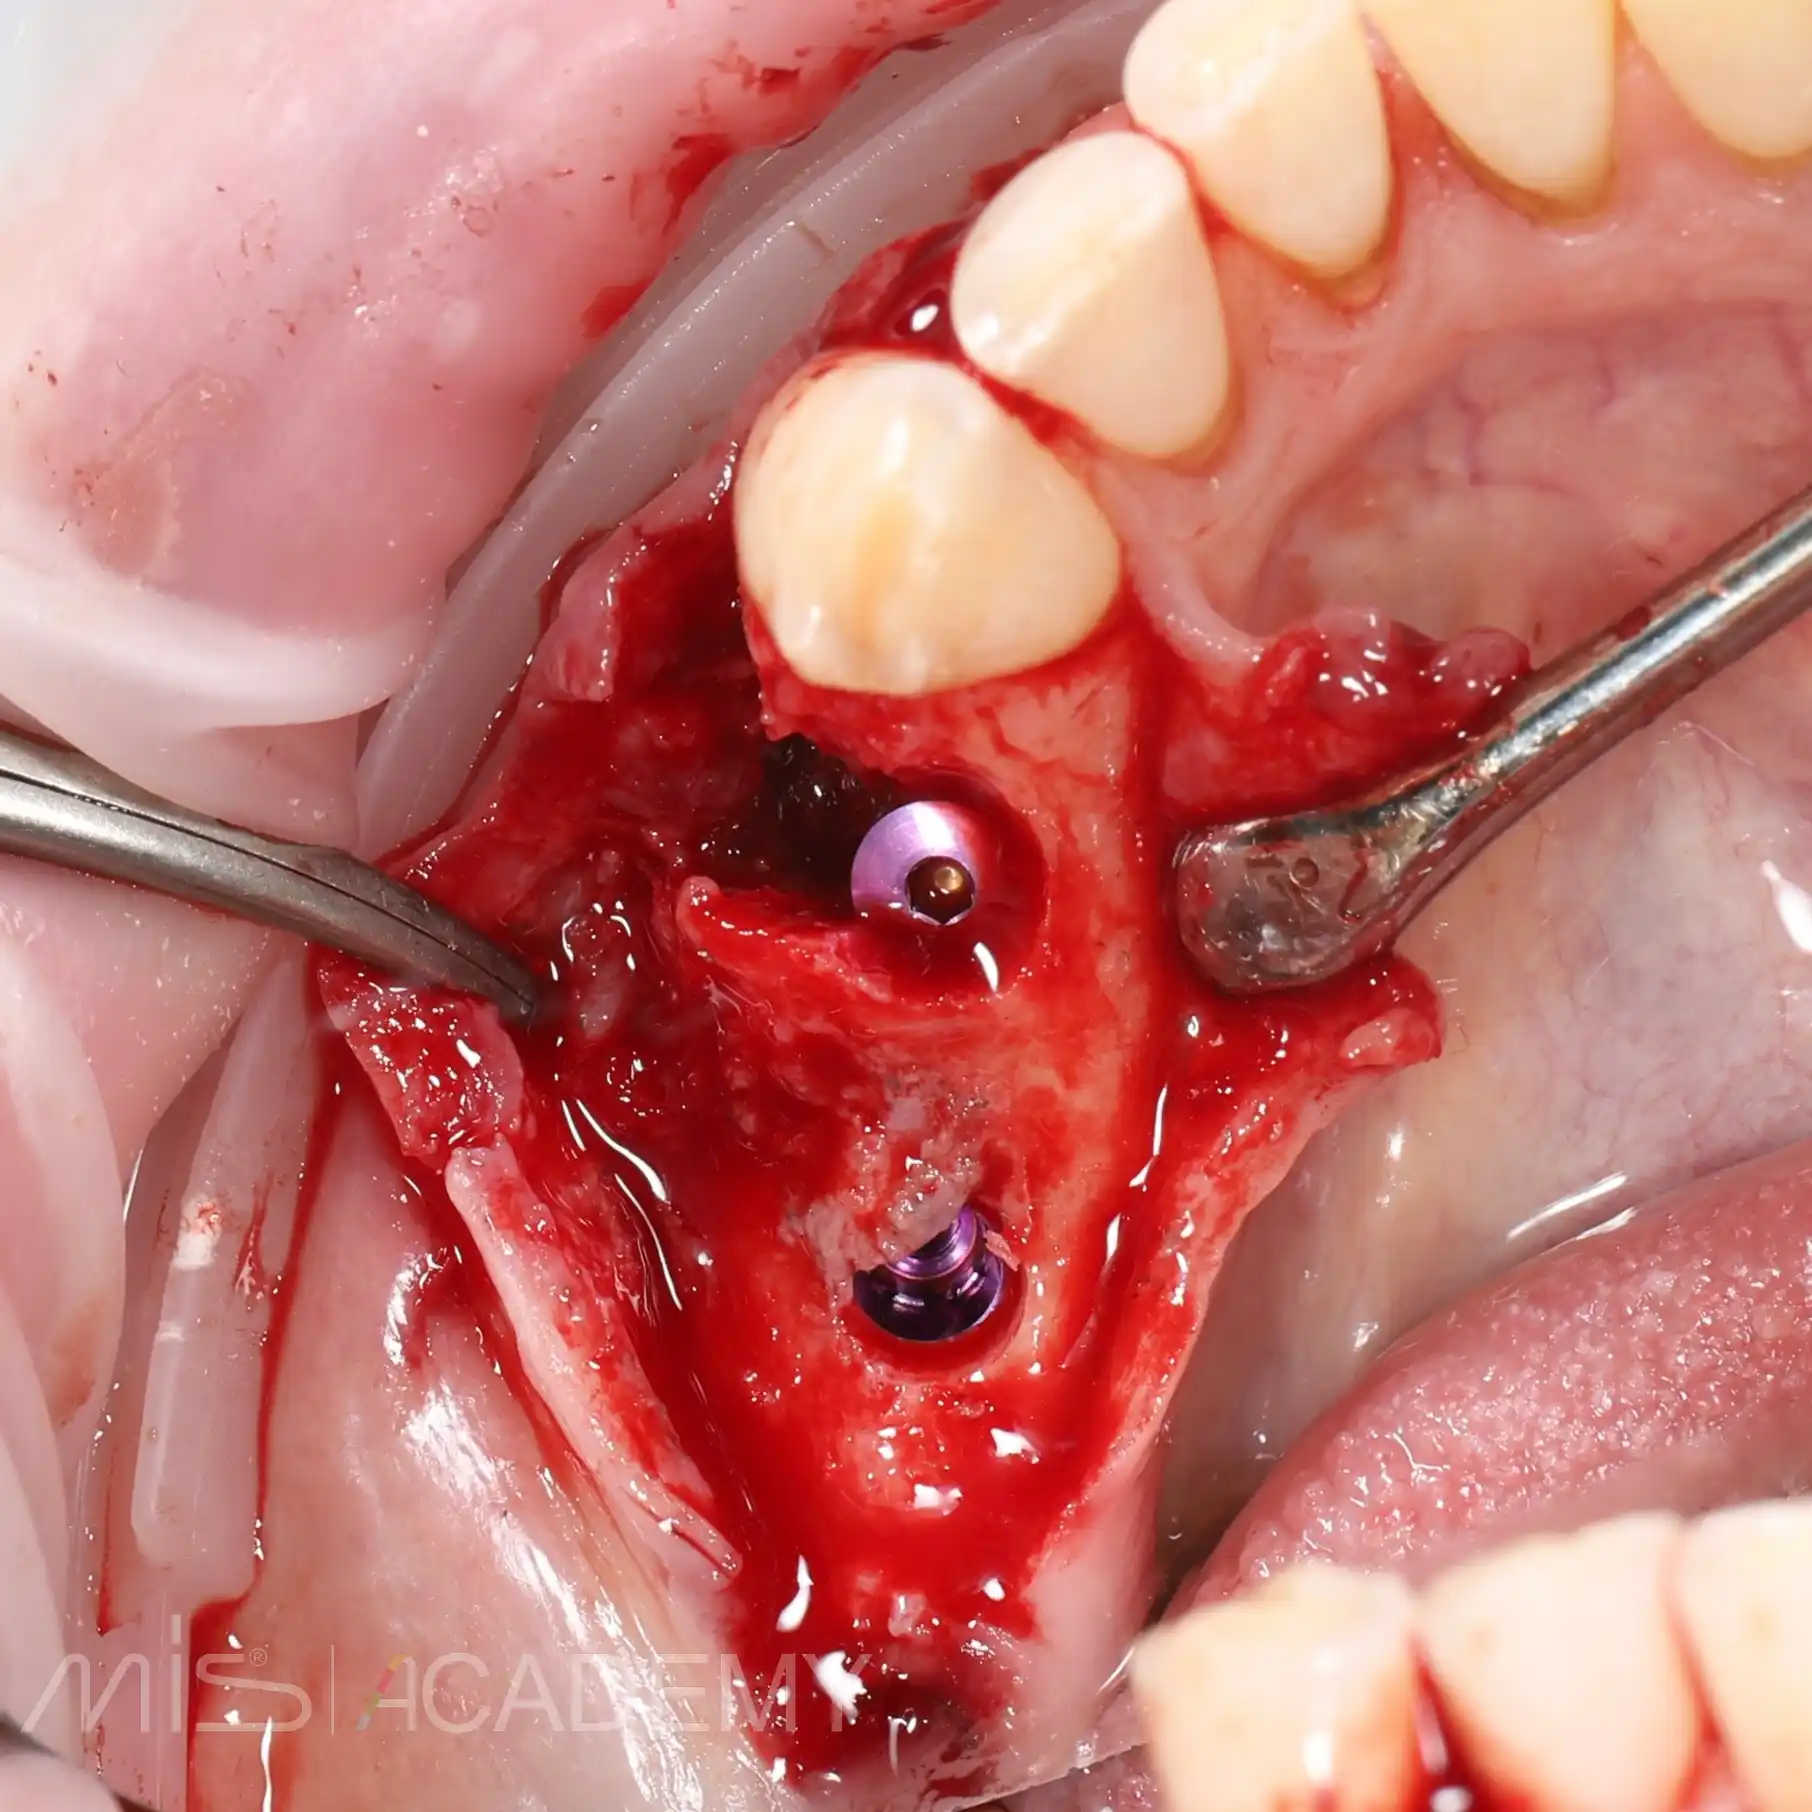

— На первом этапе был удален зуб 4.4 и установлены 2 имплантата Mis Implants C1 в области 4.4 и 4.6 (free-hand).

— Закрыли костный дефект с помощью блока из бугра ВЧ (B2S) и ССТ в области имплантатов 4.6 и 4.7.